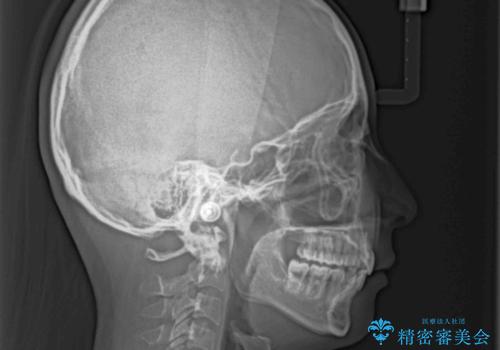

出っ歯を治したい ワイヤー装置による抜歯矯正

- 上下の出っ歯を気にして来院された患者様です。

口元を積極的に引っ込めるために、上下左右の小臼歯を4本抜歯することとしました。

右上前から2番目の歯が欠損しているため、①矯正治療により欠損部にスペースを作りインプラント補綴を行って前歯を左右対称に揃える、②左右非対称となるが、欠損補綴を行わずに排列する、のいずれかとなりますが、患者様と相談の上②にて矯正治療を行うこととしました。

変則的な歯列であったため、奥歯がしっかりと咬み合うのか、前歯はしっかりと排列できるのかと不安ではありましたが、結果としてはきれいに整った歯列にて終了することができました。